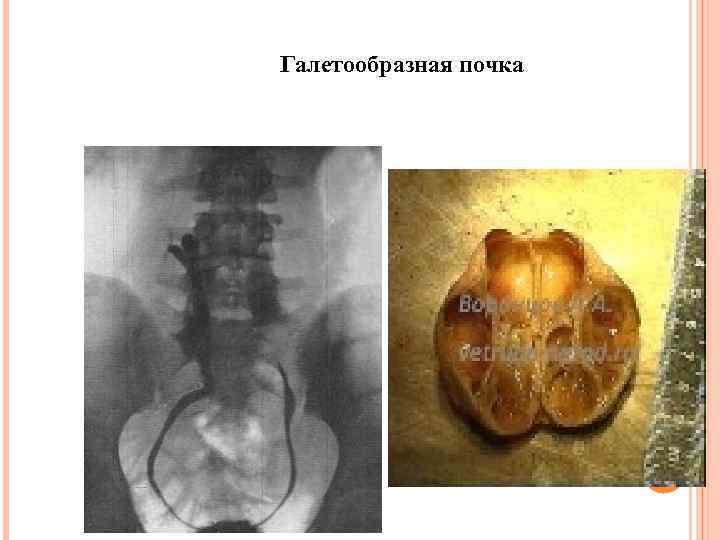

Галетообразная почка

Галетообразная почка